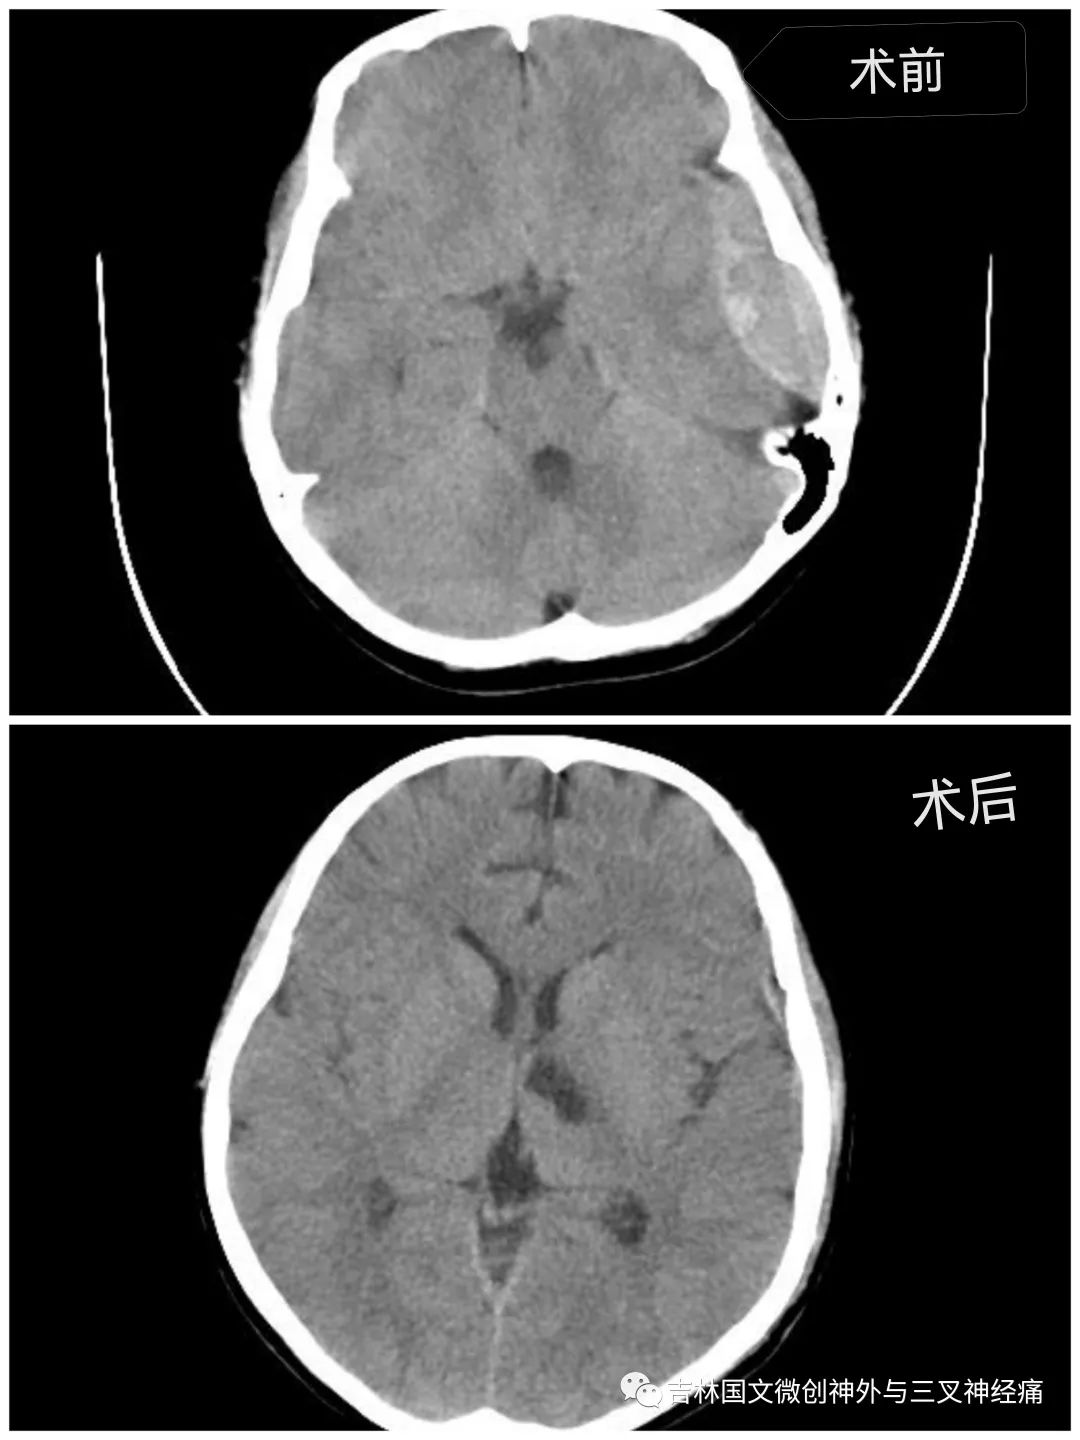

急促的車輪聲刺激著所有人的神經(jīng)?!昂⒆踊杳裕B內(nèi)出血量大,左側(cè)瞳孔散大,已腦疝,需要緊急診開顱手術(shù)”?!跗M主任向家屬交代著。家屬滿臉的焦急,并未有過多的猶豫,立即決定手術(shù)。從病人同意手術(shù)到進(jìn)入手術(shù)室,前后近用了20幾分鐘。

在王芃主任的帶領(lǐng)下,手術(shù)室的鼎力支持下,歷時(shí)近4個(gè)小時(shí),手術(shù)順利完成。由于病人腦損傷很重,一直處于昏迷狀態(tài)。為了能讓孩子的未來不至于太自卑,少受一點(diǎn)損傷,少留下一道疤痕,王芃主任帶領(lǐng)他的團(tuán)隊(duì)用盡一切辦法在努力的保護(hù)病人的氣管(嚴(yán)重腦損傷、長期昏迷的病人,為了能保證呼吸道通暢,增加病人的活命幾率,一般都需要進(jìn)行氣管切開)。